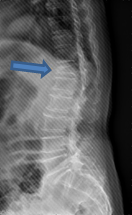

初步檢查後,老太太下肢基本上力量沒有問題,唯一就是在活動的時候,尤其是從床上起身、或是在床上翻身的時候特別疼痛不舒服,咳嗽時也會引發劇烈的疼痛感,細問之下,老太太在意識較不清楚的時候,曾有一兩次跌坐在地上的情況,當下我就大概明白有可能是哪裡發生了問題,在腰椎X光片檢查後,果然發現在胸椎第十二節的地方有一楔形的壓迫性骨折,經磁振造影檢查確定為新生的病灶後,跟家屬解釋目前的情況及可以選擇的治療方式,家屬決定接受椎體成型手術治療,手術過後疼痛馬上緩解,老人家當天下午就能下床自行坐著進食,能再次自行坐著進食,不管是病人或是家屬都對治療的效果感到非常的滿意。

| 在X光可發現胸椎第十二節有一楔形的壓迫性骨折病灶。 |